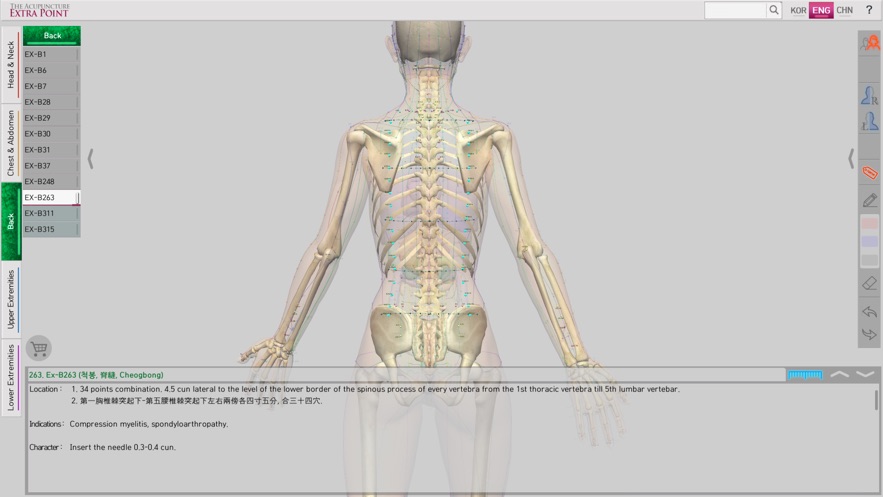

‘The Acupuncture of Extra Point’ was created by integrating Extra Point from the past, and the newly discovered New Point together as one product. It allows for easy comparison because it expresses 14 Main Acupuncture Point Meridian and the Extra Acupuncture Point together in a male and female 3D model. Easily zoom in and out with multi-touch so you can see the exact location of The Acupuncture Point. It is recommended for people who want to see both 14 Main Acupuncture Point Meridian and the Extra Acupuncture Point at the same time. Contents include accurate location, based book, function and character (how to use). Released in Korean, Chinese and English, which allows it to be used across the world! With realistic skin, bone, and internal organs in 3D human body model, everything is distinguished by rich colors so it is very easy to see. It is based on The International Standard Acupuncture Points of WHO, WHO`s International Standard Terminologies on Traditional Medicine in The Western Pacific Region, The acupuncture textbooks of the university of Asian Medicine and 'Huangdi Neijing - Lingshu’. It is supervised by professors and Korean medical doctors from Korea Medical University. * 14 Main Acupuncture Point Meridian - 12 Main Acupuncture Point, Governor Vessel (GV) Acupuncture Point, Conception Vessel(CV) Acupuncture Point.- See The Meridian 2.0

‘The Acupuncture of Extra Point’ is the only product in the world that expresses the Extra Acupuncture Point on male and female 3D human models.

‘The Acupuncture of Extra Point’ is easy to use because it displays The Extra Acupuncture Point on 3D human body model. As well, the Extra Acupuncture Point and 14 Main Acupuncture Point Meridians are displayed together with the accuracy, so you can easily compare.

In 'The Acupuncture of Extra Point’, the skin, bones, and internal organs of the 3D human model look realistic. The 14 Main Acupuncture Point Meridians and the Extra Acupuncture Point are distinguished by rich colors so they are very easy to see.